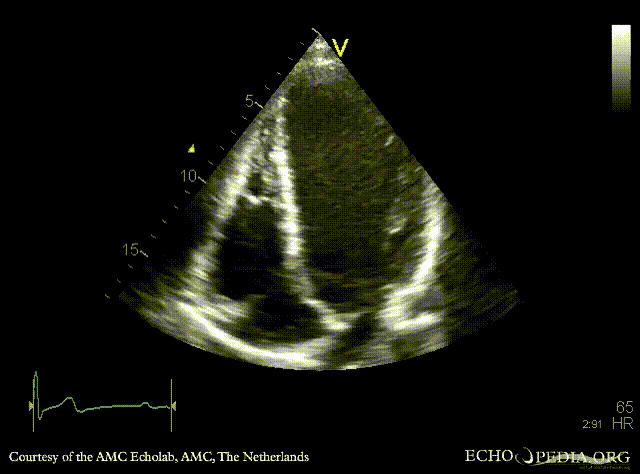

E00233.gif E00234.gif

A4CH: left ventricle dilatation A3CH: Color Doppler, severe aortic regurgitation